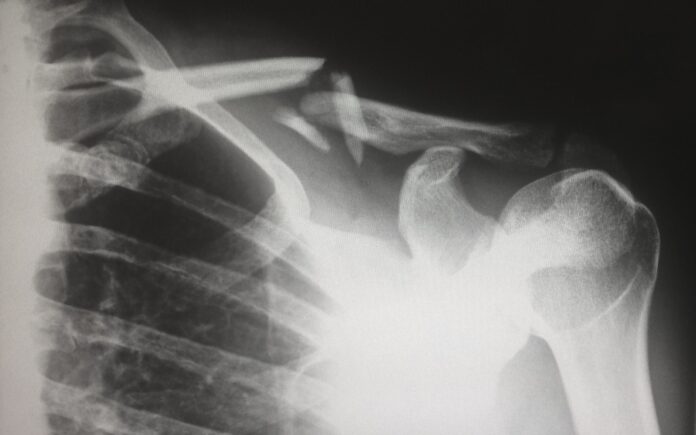

U kineskoj provinciji Džeđijang, tim ortopedskih hirurga predstavio je medicinski izum koji bi mogao da promeni način lečenja preloma širom sveta. Reč je o bio-lepku „Bone-02“, prvom materijalu ove vrste koji u svega nekoliko minuta spaja slomljene kosti bez potrebe za metalnim pločicama, šrafovima ili naknadnim operacijama.

U prvim kliničkim ispitivanjima na više od 150 pacijenata, „Bone-02” je pokazao zavidnu otpornost: spaja fragmente kosti za dva do tri minuta i postepeno se razgrađuje dok kost prirodno zarasta, čime eliminiše potrebu za dodatnim hirurškim zahvatom.

Lekari ističu da ova tehnologija ne samo da smanjuje vreme provedeno u operacionoj sali i rizik od infekcija, već može i da ubrza oporavak i smanji troškove lečenja, piše Global tajms.

Za razliku od konvencionalnih metoda, pacijenti ne moraju da prolaze kroz drugu operaciju kako bi im se uklonile mtelne pločice. Ako se dugoročne studije pokažu uspešnim, „Bone-02” bi mogao da postane standardna procedura za mnoge tipove preloma, posebno u udaljenim ili slabije opremljenim bolnicama, gde je kompleksna ortopedska oprema teško dostupna.